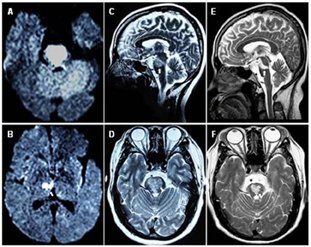

磁共振检查结果显示双侧脑桥和右侧丘脑符合急性脑梗死表现。诊断为脑梗死、高血压、肺部感染,根据症状和查体结合辅助检查诊断为完全性闭锁综合征。

当地医院急诊头颅CT显示未见脑出血。广东省某三甲医院2019年10月17日头颅MRI+MRA+DWI示:右侧丘脑及桥脑区梗塞;脑动脉硬化,基底动脉远端闭塞。10月22日脑血管造影(DSA):I型主动脉弓;基底动脉远端次全闭塞,前向血流TICI1级;右侧椎动脉V4段闭塞,左侧椎动脉开口迂曲;双侧PcomA开放,双PcomA近端变细。10月22日心脏彩超示:风湿性心脏病,轻度二尖瓣狭窄并中度反流,轻度主动脉瓣狭窄并轻度反流,轻度三尖瓣反流,轻度肺高压。

(3)外院头颅MR检查提示右侧丘脑及双侧脑桥区急性脑梗死。